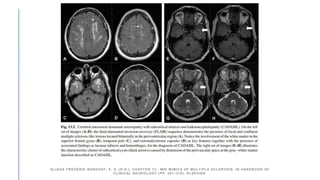

Multiple ischemic

lesions (A-B), post-

contrast

leptomeningeal

enhancement (C),

multiple focal stenosis

of bilateral MCA on TOF

MRI (D).

PRIMARY ANGIITIS OF THE CENTRAL NERVOUS SYSTEM MAGNETIC RESONANC E IMAGING

SPECTRUM OF PARENCHYMAL, MENINGEAL, AND VASCULAR LESIONS AT BASE LINE.

(N.D.). STROKE. DOI:10.1161/STROKEAHA.116.016194

Right frontal acute

intraparenchymal

hemorrhage (A), 3 months

later on (B-C) showing post

contrast enhancement.

PRIMARY ANGIITIS OFTHE CENTRAL NERVOUS SYSTEM MAGNETIC RESONANC E IMAGING SPECTRUM OF PARENCHYMAL, MENINGEAL, AND VASCULAR LESIONS AT BASE LINE. (N.D.). STROKE. DOI:10.1161/STROKEAHA.116.016194 Multiple ischemic lesions (A-B), post- contrast leptomeningeal enhancement (C), multiple focal stenosis of bilateral MCA on TOF MRI (D).

• 25.

PRIMARY ANGIITIS OFTHE CENTRAL NERVOUS SYSTEM MAGNETIC RESONANC E IMAGING SPECTRUM OF PARENCHYMAL, MENINGEAL, AND VASCULAR LESIONS AT BASE LINE. (N.D.). STROKE. DOI:10.1161/STROKEAHA.116.016194 Right frontal acute intraparenchymal hemorrhage (A), 3 months later on (B-C) showing post contrast enhancement.